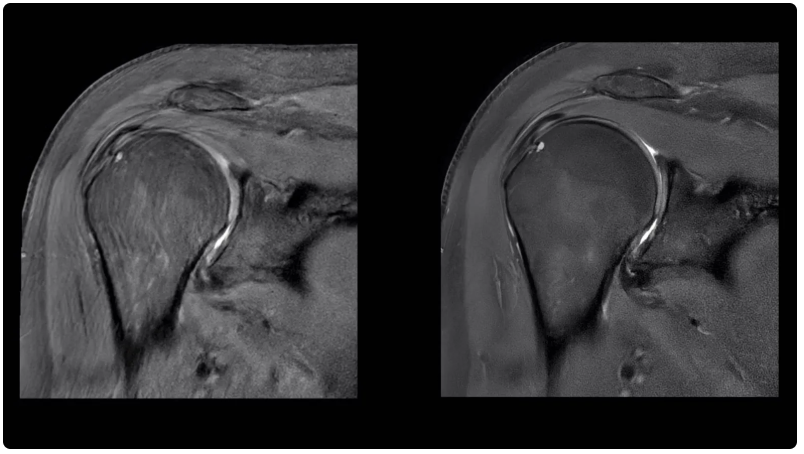

自2022年MedTech Dive首次分析FDA數(shù)據(jù)以來,通用電氣醫(yī)療集團(GE Healthcare)和西門子醫(yī)療集團(Siemens Healthineers)的人工智能設備數(shù)量位居榜首。截至2024年8月7日,通用電氣醫(yī)療集團共有81臺人工智能設備獲得授權。其旗艦人工智能產(chǎn)品之一 Air Recon DL 于 2020 年推出。通用電氣醫(yī)療保健公司的人工智能宣傳負責人Jan Beger說,這種算法可以提高圖像質量,并將核磁共振掃描時間最多縮短50%。截至 2024 年 10 月,該公司已使用該軟件掃描了 3400 多萬名患者。Beger 將通用電氣醫(yī)療保健公司的人工智能方法分為三類:用于提高成像效率的 Air Recon DL 等產(chǎn)品、從各種來源提取數(shù)據(jù)以幫助臨床醫(yī)生做出決策的人工智能以及用于規(guī)劃的企業(yè)級系統(tǒng)。有時,這些功能內置在公司銷售的成像設備中。在其他情況下,通用電氣醫(yī)療保健公司會將這些功能作為單獨的訂購產(chǎn)品出售。“總的來說,人工智能的理念其實是,我們如何才能將冗余、重復、平凡的任務自動化?”Beger說。

肩部掃描圖像(左)與使用人工智能功能銳化后的相同圖像(右)進行對比。Air Recon DL 是通用電氣醫(yī)療集團的旗艦人工智能產(chǎn)品之一,旨在提高圖像質量,縮短核磁共振成像掃描時間。